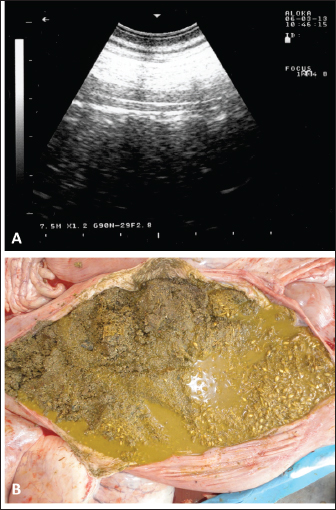

Sonographic and postmortem findings are summarized in Table 2. In cases of camels presented with a history of pica and with decreased or total absence of feces, the obstructing foreign body was imaged in 10 of the 25 camels (40%) occluding completely or partially the intestines that may be confirmed at abdominal surgery (Figs. 2, 3, and 6). Foreign bodies within the rumen could not be visualized with ultrasound owing to the gas content. In cases where the rumen is impacted by sand, small pin-points revealing acoustic enhancement were imaged in 5 (20%) of the camels. An example of these cases is shown in Figure 7. Foreign bodies were removed from the rumen or intestines at exploratory rumenotomy and laparotomy, which included plastics, cloths, sand, mud, robes, wool balls, glasses, or even metallic objects that were blunt or sharp (Figs. 8 and 9).

Fig. 7. Ultrasonographic and postmortem findings in an adult female camel with a history of pica and decreased fecal output and abdominal distension. Image (A) was taken using a 3.5 MHz sector transducer and shows sonography of the rumen from the left lower abdomen where several pin-points acoustic shadowing were imaged. Image (B) shows large amounts of sand within the rumen detected at postmortem examination.